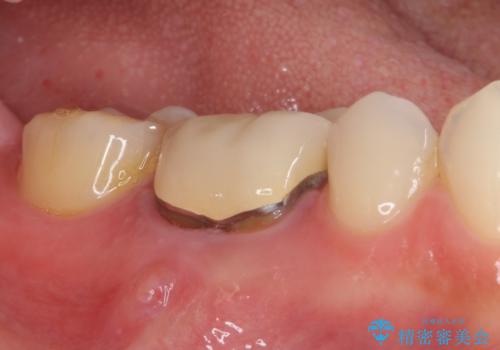

- 歯肉の退縮に伴い、金属を用いたクラウンの縁が見えてしまうことを気にして来院された患者様です。

歯肉には膿の出口が見られ、レントゲン写真からは歯根周辺に病変が認められたため、まずは根管治療を行い、その後フルジルコニアクラウンにて補綴することとしました。